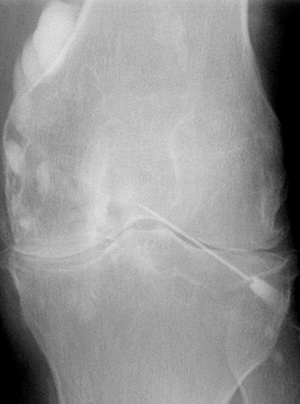

Βλάβες χόνδρου |

– γόνατος |